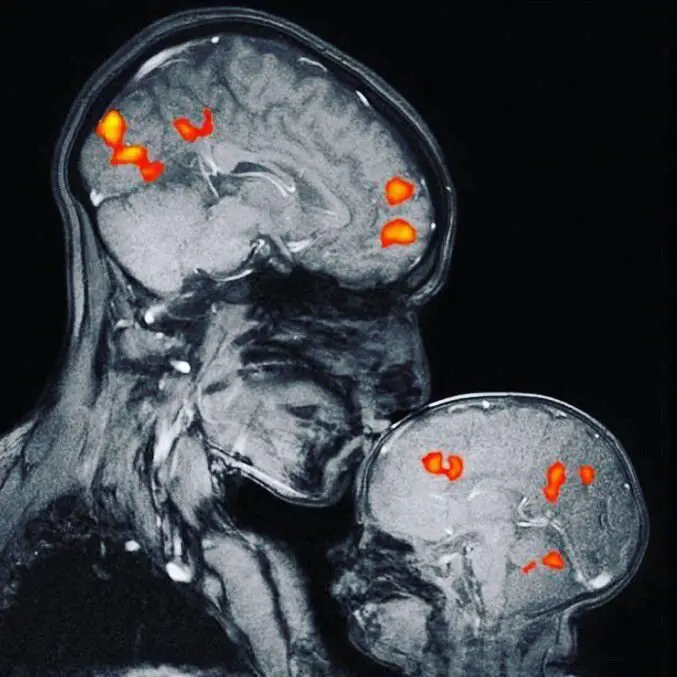

Cette hormone peut joue un rôle crucial dans la régulation de l’humeur et le traitement de la dépression. En effet, l’ocytocine agit en interagissant avec les récepteurs du cerveau impliqués dans la modulation de l’anxiété et de la dépression, ce qui réduit les symptômes dépressifs. De plus, l’ocytocine favorise la formation de nouvelles connexions neuronales, ce qui entraine une excellente plasticité cérébrale et la récupération de la dépression.

L’ocytocine agit sur plusieurs mécanismes qui aident à combattre la dépression. C’est ainsi qu’elle influence les niveaux de certains neurotransmetteurs ; comme nous l’avons vu plus haut ; tels que la sérotonine, la dopamine et l’ocytocine elle-même. En modulant leur activité, l’ocytocine rétablit l’équilibre chimique du cerveau.